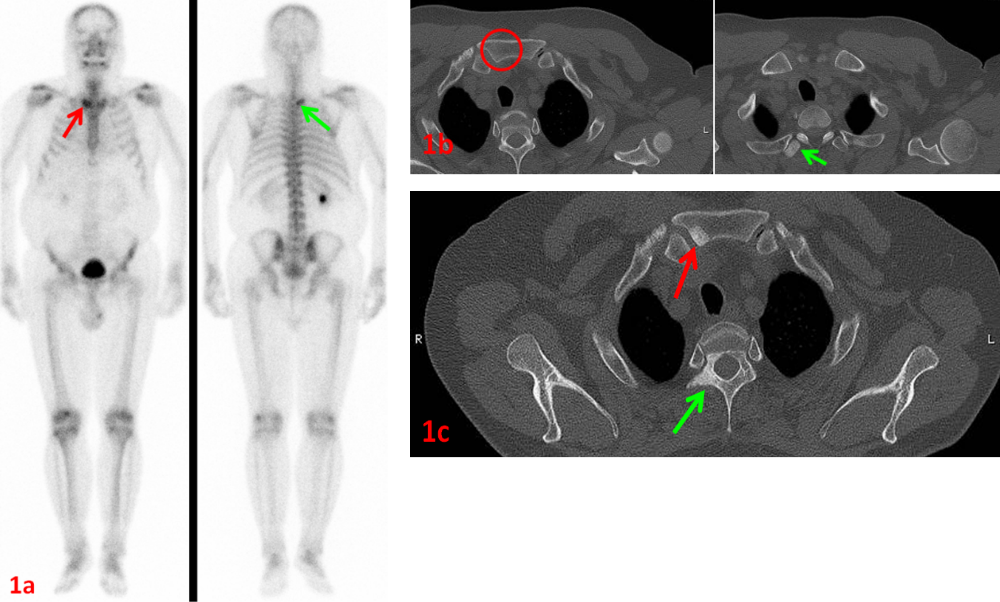

老年男性,右肺腺癌,ECT示胸骨柄右側(cè)(圖1a紅箭)、T2右側(cè)橫突(圖1a綠箭)代謝異常,考慮骨轉(zhuǎn)移。同期CT示胸骨柄未見異常(圖1b紅圈),T2右側(cè)橫突骨質(zhì)密度略增高(圖1b綠箭)。

6個月后復(fù)查CT示胸骨柄(圖1c紅箭)、T2右側(cè)附件(圖1c綠箭)病灶骨質(zhì)硬化,證實了ECT診斷的早期敏感性和準(zhǔn)確性。